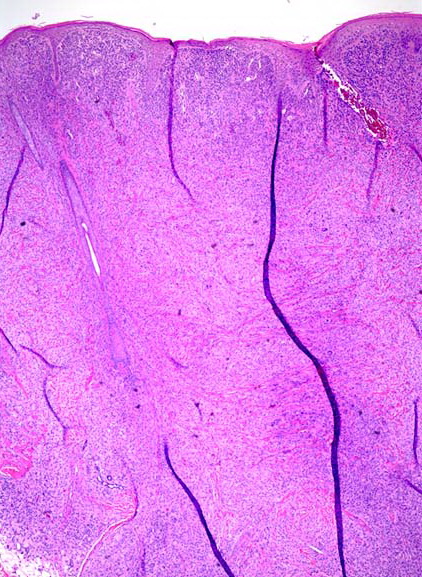

Biopsy sections of JXG lesions show a feature that is common to many NLCHs, that is, a nonepidermotropic histiocytic infiltrate lacking Langerhans granules. Early lesions of JXG are characterized by a monomorphous, non-lipid-containing histiocytic infiltrate that occupies at least the upper half, and sometimes the entire thickness, of the dermis. Mature lesions

contain foam cells, foreign-body giant cells, and Touton giant cells, mainly distributed in the superficial dermis and on the border of the infiltrate. Lymphocytes, eosinophils, and neutrophils are variably associated. Older lesions may show fibrosis. In mature lesions, fat stains yield positive results. The majority of JXG lesional biopsy sections stain positive for CD68/Ki-M1P and factor XIIIa but negative for CD1a and S100 protein.